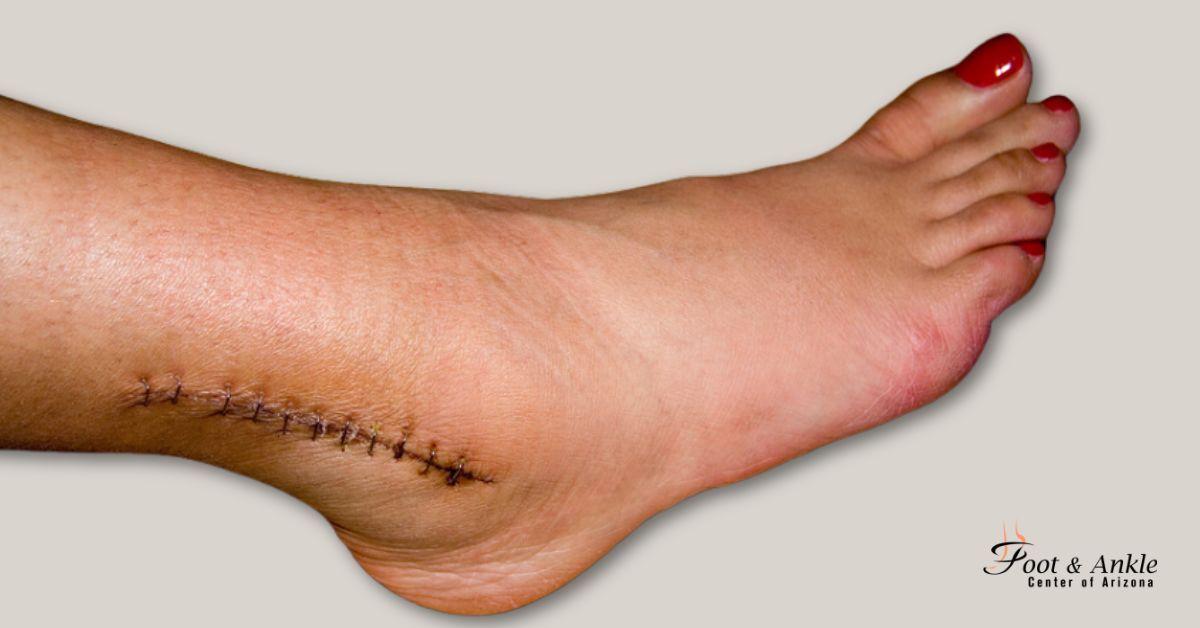

When a fibula or tibia is fractured, it can heal with a stable internal fixation screwed onto the bone during surgery to help align the bones properly. This will take a few weeks and patients should avoid weight on their ankle for 3 to 10 weeks, depending on the severity of the fracture. In addition, patients should wear a cast or boot and also attend physical therapy for optimal results.